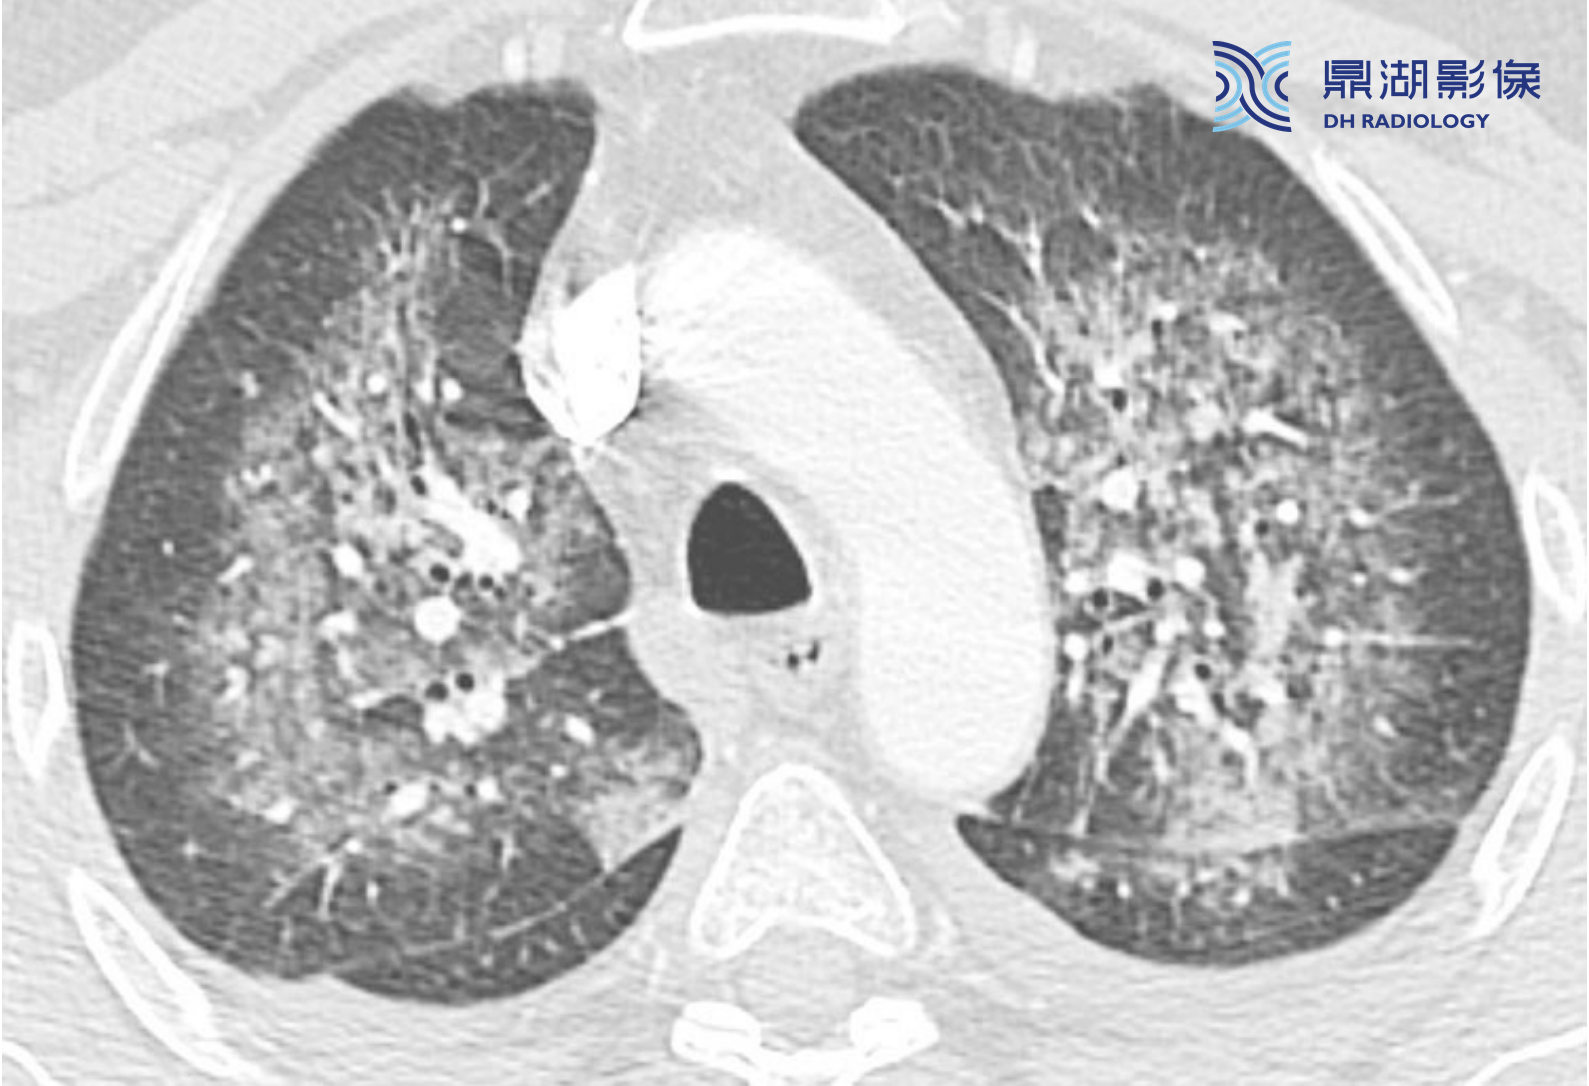

20d11bbae20d111476bb8d5e7b7b98ac.png

865b77b4654914c49e88ae84b97e9134.png

弥漫性肺泡损伤导致的急性呼吸窘迫综合征(ARDS)的典型表现。本例为败血症患者,HRCT显示弥漫性实变和GGO,虽然为非特异性,却是DAD和ARDS的典型表现。

注意:肺外周和肺下垂区受累更为严重。